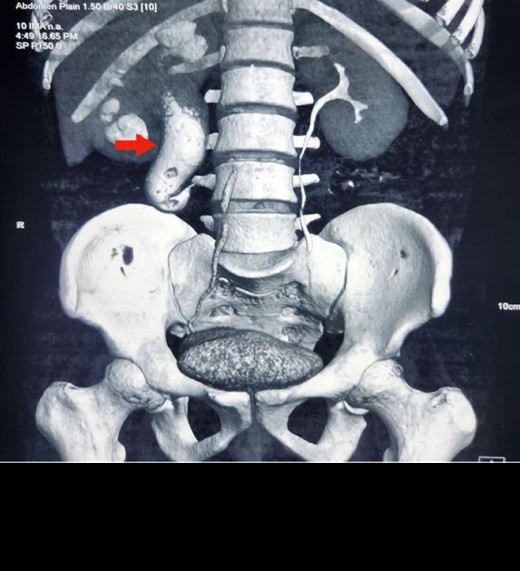

An abdominal ultrasound was done, which revealed moderate right-sided hydronephrosis and proximal dilated ureter. A routine X-ray kidney–ureter–bladder (KUB) showed no obvious radio opaque shadow in the renal pelvis. A contrast-enhanced computed tomography (CECT) KUB was done, which showed moderate right Hydroureteronephrosis (Fig. 1) extending to the proximal ureter with papillary necrosis, consistent with retrocaval ureter (Fig. 2).

Reconstruction image of CECT KUB showing retrocaval ureter (arrow) and hydronephrosis of right kidney with dilated proximal ureter.